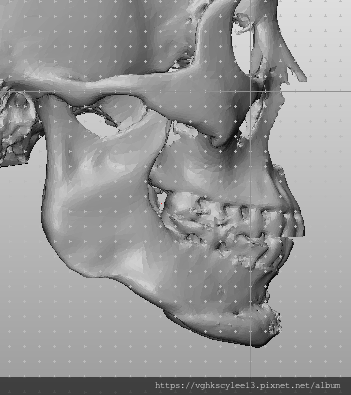

成型的下巴植體手術常遇到的就是不吻合臉型, 甚至可能因此歪斜(下圖),因此客製化假體相當重要避免術後不吻合或嘴邊斷層的嘎尬。

下圖重修歪斜下巴的過程:

李醫師針對重修下巴(上圖)的求美者有堅持:

1.務必3D電腦斷層評估與設計

2.配合工程師計算出落差數據

3.患者本人與照片分析評估及溝通

4.精準客製化適合假體![]()

下圖:不對稱下巴骨架,透過列印技術可以做出調整下巴歪斜的假體組合。

歪斜下巴調整性假體設計

下圖範例:歪斜不對稱下巴經3D導航客製化導航矯正性假體